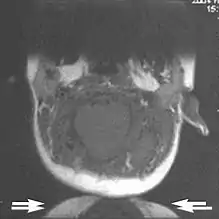

A wrap-around artifact also known as an aliasing artifact, is a result of mismapping of anatomy that lies outside the field of view but within the slice volume.[4] The selected field of view is smaller than the size of the imaged object. The anatomy is usually displaced to the opposite side of the image (Figs 6 and 7). It can be caused by non-linear gradients or by undersampling of the frequencies contained within the return signal.[1] The sampling rate must be twice the maximal frequency that occurs in the object (Nyquist sampling limit). If not, the Fourier transform will assign very low values to the frequency signals greater than the Nyquist limit. These frequencies will then ‘wrap around’ to the opposite side of the image, masquerading as low-frequency signals. In the frequency encode direction a filter can be applied to the acquired signal to eliminate frequencies greater than the Nyquist frequency. In the phase encode direction, artifacts can be reduced by an increasing number of phase encode steps (increased image time). For correction, a larger field of view may be chosen.[1]